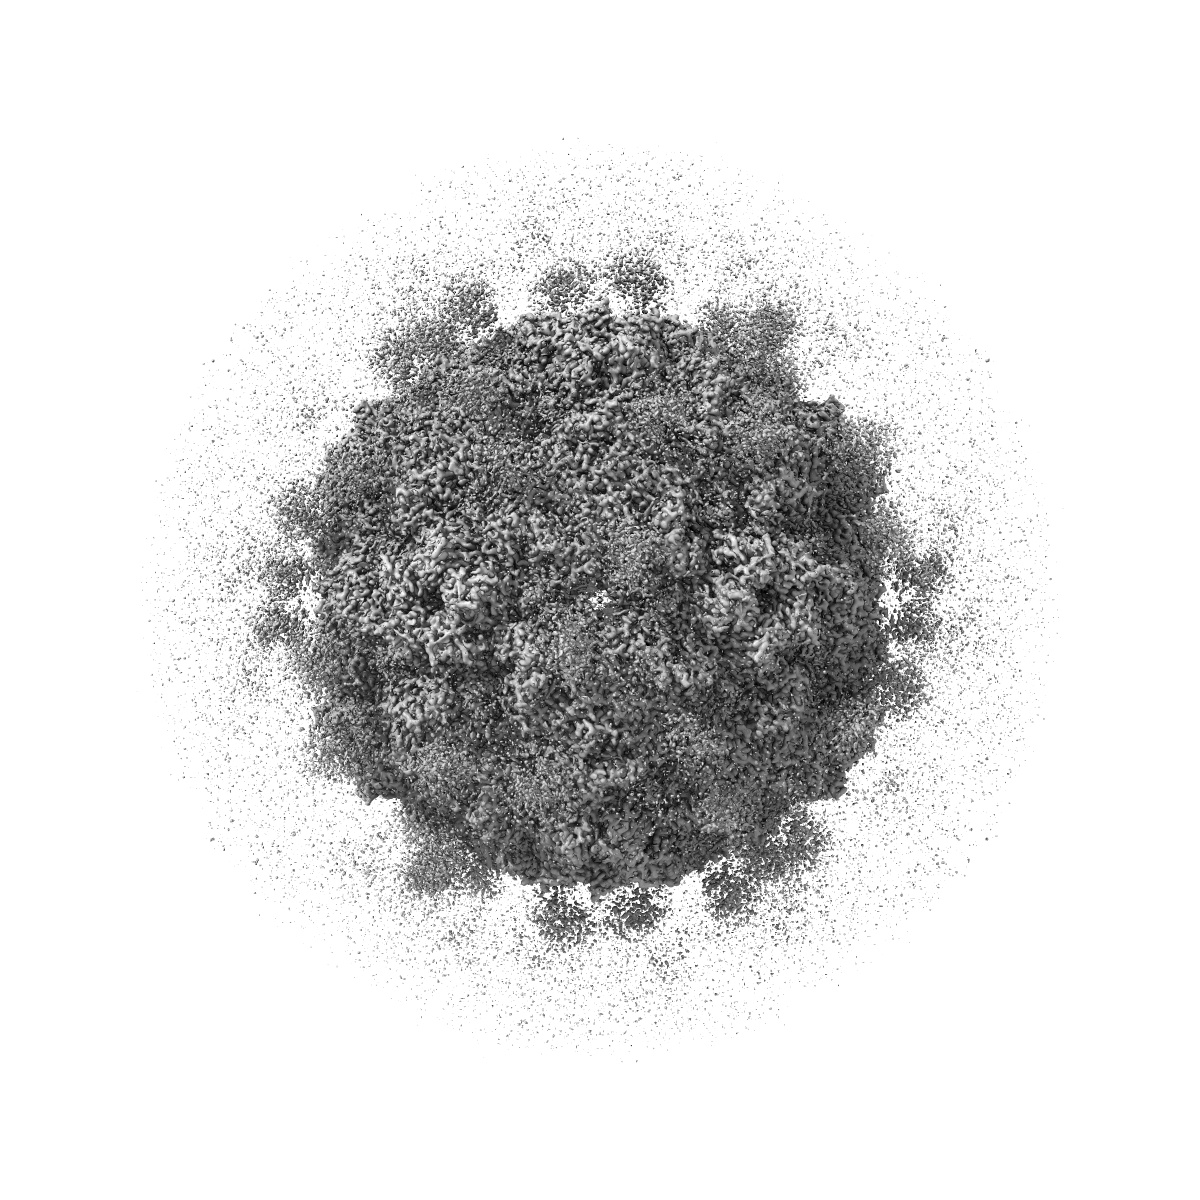

Cryo-EM structure of enterovirus A71 empty particle in complex with Fab h1A6.2

Single-particle2.98 Å

Sample: Enterovirus A71 empty particle in complex with Fab h1A6.2

Broadly therapeutic antibody provides cross-serotype protection against enteroviruses via Fc effector functions and by mimicking SCARB2.